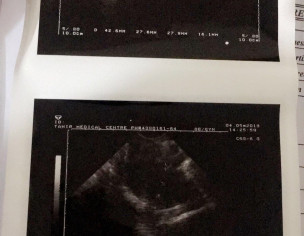

I just want to know that my reports are normal?

one mature egg is visulized. Normal Ultrasound

Yess this is normal.

Yes they r normal